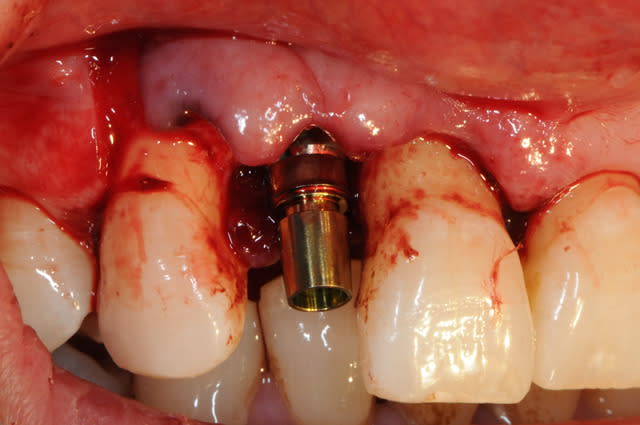

la chir...

extraction de 12 et 22 pour commencer et pour connaitre la limite maxi d'implantation dans la crête osseuse.

grosse déception quant à la table externe au niveau de 11

pour les axes, j'avoue que je me suis fait avoir comme une bleusaille (mais bon, j'en suis une), je me suis un peu laisser embarquer par l'axe des alvéoles. c'est dure l'implanto.